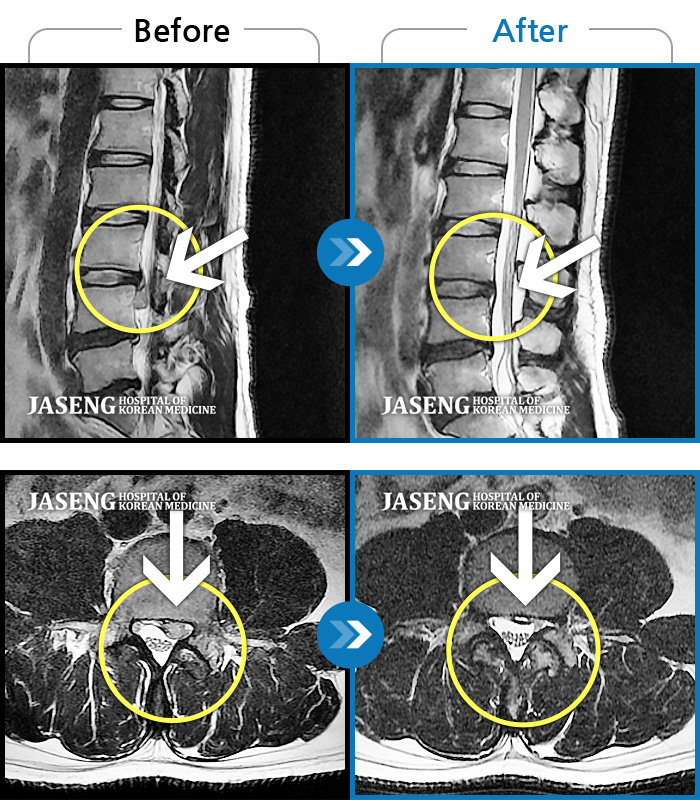

MRI 치료사례

좌측 하지 방사통, 보행 불가, 하지 근력 저하